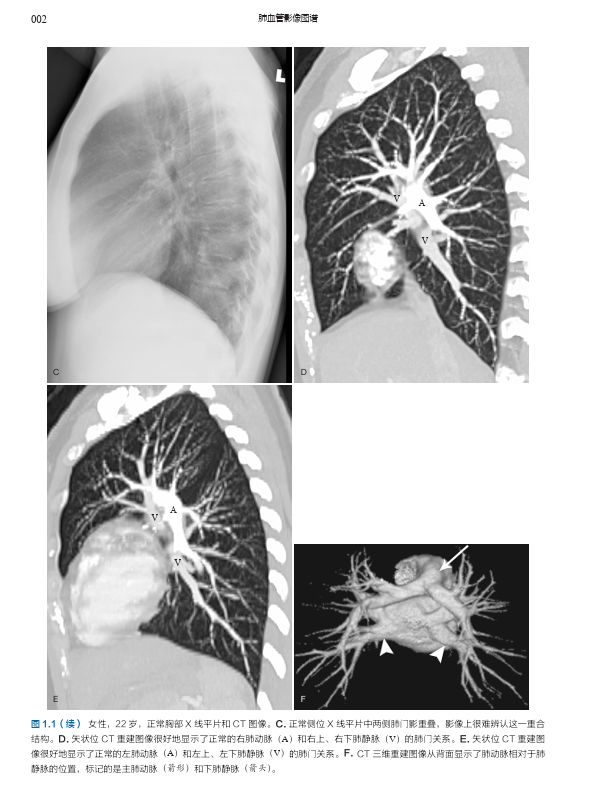

本书是由哈佛大学医学院附属麻省总医院 Conrad Wittram 编写的有关肺血管疾病的综合影像图谱,内容包括肺血管正常解剖、先天性肺部疾病和心脏疾病的肺血管变化、特定类别的肺血管疾病(如栓塞、血栓形成、血管炎、动脉瘤和静脉瘤、感染、肿瘤、肺高血压等)、创伤与介入治疗相关肺血管问题,以及全身和肺部疾病的肺血管变化的影像学表现及特点。本书内容翔实,编排简明清晰,图文配合,每一页上都有详细的、清晰标记的高质量影像图,展示了 X 线片、血管造影、多层螺旋 CT、MRI、超声和核素显像等多种成像方式下的影像表现,配以绘图及指示性箭头等,使得影像特征更加清晰;文字精要,突出了最相关的重要信息。

肺动脉 001